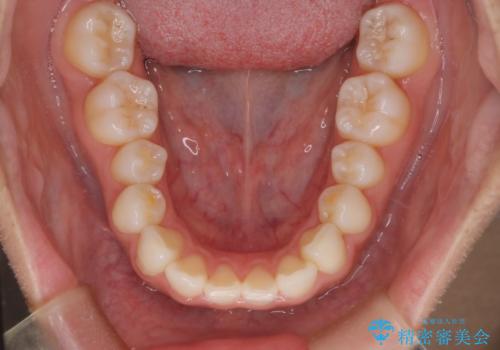

【インビザライン】前歯の後戻りを再矯正

- 前歯が出ていることを主訴に来院されました。検査の結果、口元が標準より出ているわけではなかったため今回はIPRと拡大をし、非抜歯で治療を行いました。

非抜歯でも歯軸の向きを改善したことで前歯が下がり、出っ歯に見えてしまうという主訴が改善しました。